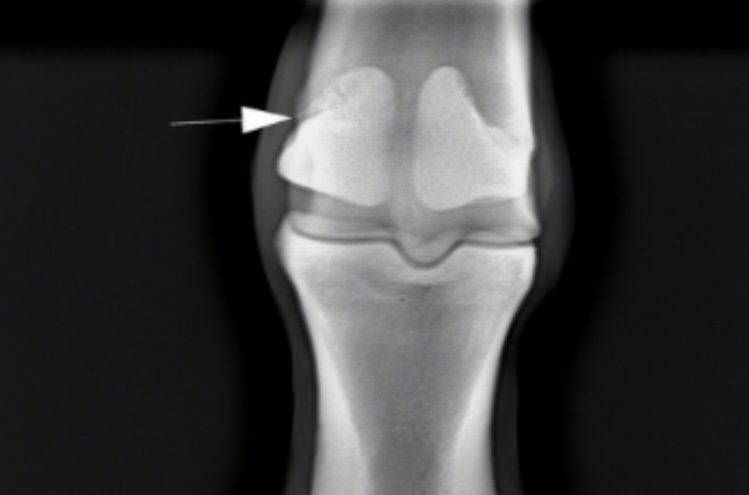

Трещина сесамовидной кости

Прошу помощи ,приезжал вет ,делал рентгены ,так как конь начал прихрамывать и выяснилось что есть трещина .Опухоли нет ,не жалуется....но точно что делать дальше не сказал

Я бы даже сказала, что не трещина, а перелом. Там осколок.

Вы видимо не понимаете разницы между трещиной и осколком. То, что на снимке ТС -- это осколок, а не просто трещина. Т.е. фактически перелом. И при движении он может сместиться. И тогда все разговоры о вреде стояния для контрактуры станут, мягко говоря, неуместными. Потому что лошадь останется инвалидом на всю жизнь.